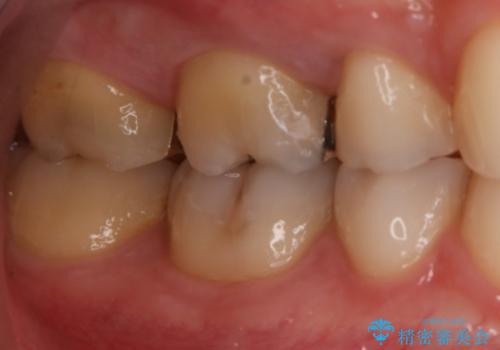

- 右上6番の銀歯のやりかえを希望し来院された患者様です。

切削量や形状からインレーでの治療を計画しました。

ご本人が金歯を希望されたため、ゴールドインレーでの治療を選択しました。